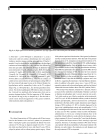

A 48-year-old female with AGC presented dizziness and diplopia for 5 days and a 20 kg weight loss. Neurologic exam showed nystagmus and gaze disturbance. Her symptoms improved after daily parenteral injection of thiamine 100 mg for 17 days. A 58-year-old female with AGC presented with sudden disorientation, confusion and 15 kg weight loss. Neurologic exam showed gaze limitation and mild ataxia. Despite daily parenteral injection of thiamine 100 mg for 4 days, she died 5 days after the onset of neurologic symptoms. Combining the cases noted in the literature review with our 2 cases, the 7 gastric cancer cases and 2 colorectal cancer cases related to WE showed similar clinical characteristics; 1) a history of long-period malnutrition and weight loss, 2) relatively typical neurologic signs and symptoms and 3) specific magnetic resonance image findings. Except for 2 patients who had irreversible neurologic symptoms, the other 7 patients were improved with prompt thiamine treatment.